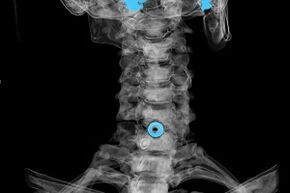

- MRI (chụp cộng hưởng từ) của cột sống cổ. Một phương pháp cho phép bạn xem cấu trúc xương, đĩa đệm thoát vị, kích thước và hướng phát triển của chúng.